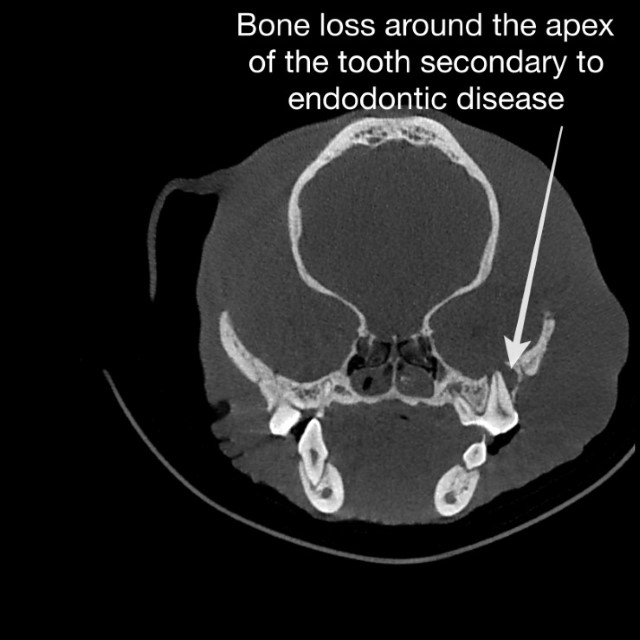

3D images captured with the Planmed Verity CBCT confirmed the diagnosis of severe endodontic disease, causing a tooth root “abscess.” Rapid capture of a CBCT image had the clear advantage of uncovering the pathology that caused the facial swelling over the intraoral X-ray, which appeared normal.

Without the rapid 3D image capture, what would have been the next course for Fabio? Traditional CT scans can be an option, but ultimately, the large slices of a CT scan image are not ideal for diagnosing dental disease compared to the thin, sharp image slices of CBCT image. The CT imaging process involves more time, delaying diagnosis and treatment, and more costly for the pet parent.

Dr. Buelow explained, "This is a serious issue for brachycephalic breeds. We should not be treating these breeds without CBCT as traditional dental x-rays miss too much pathology. Fabio is an excellent case to justify that CBCT is a more sensitive diagnostic tool, not only for brachycephalic breeds but for all of our patients."